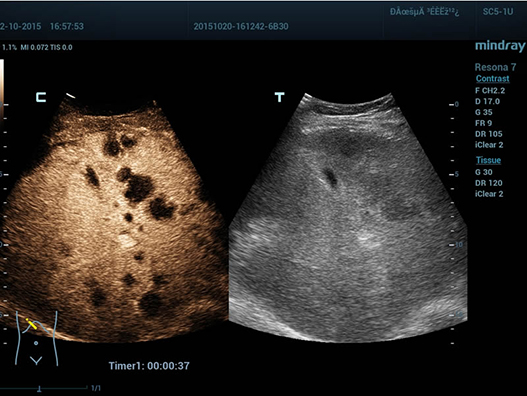

Sejak didirikan, Mindray terus mencari cara baru untuk meningkatkan keandalan diagnostik. Didukung Teknologi ZONE Sonography? terkini, platform ZST+ baru Resona 7 meningkatkan kualitas gambar ultrasound melalui pengambilan zona dan pemrosesan data saluran.

Selain kualitas gambar premium, Resona 7 juga meningkatkan kemampuan penelitian klinis dengan V Flow revolusioner untuk evaluasi hemodinamika vaskular, serta pengambilan penampang tercanggih dari rangkaian data 3D untuk diagnosis CNS pada janin. Kombinasi pengoperasian multisentuh berbasis gerakan yang paling intuitif dengan semua fitur klinis penting membuat Resona 7 menjadi gebrakan baru dalam inovasi ultrasound.